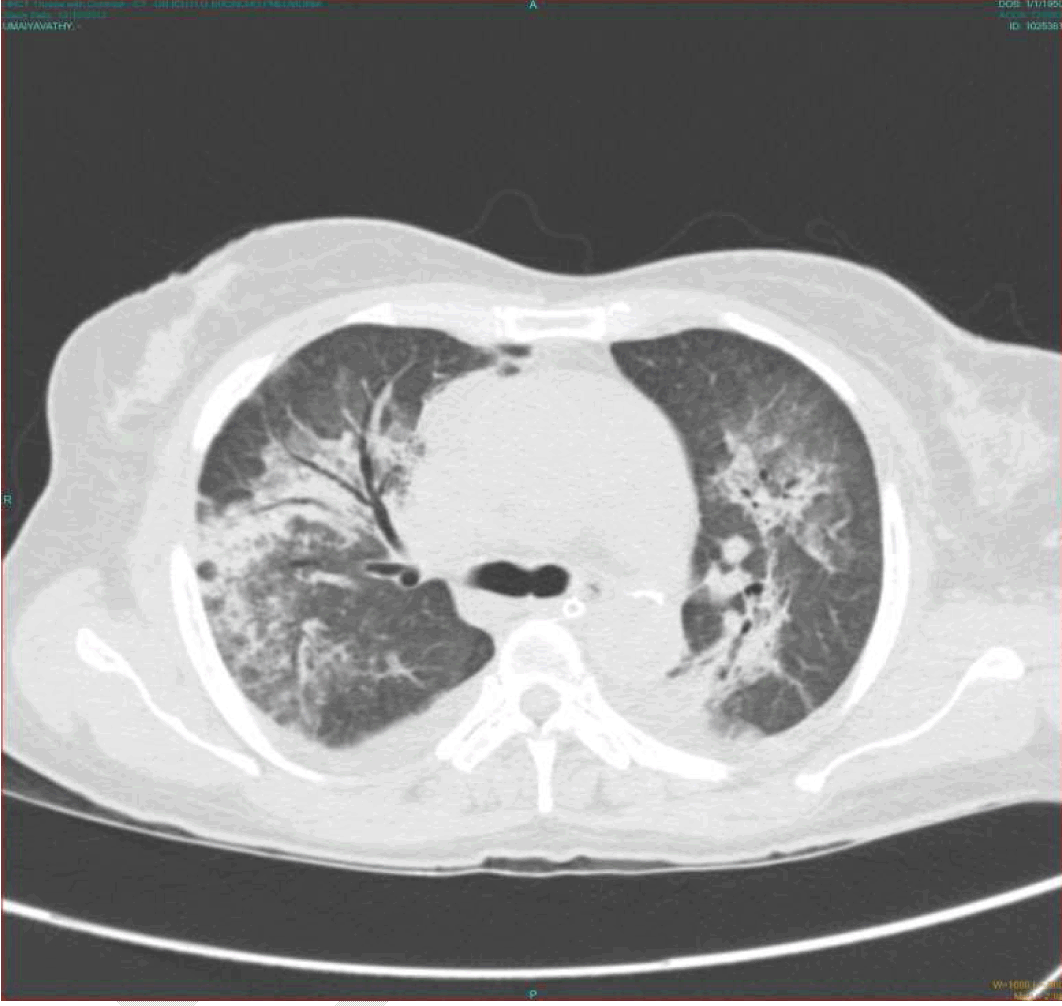

A 62-year-old female, farmer by occupation presented to the emergency department with history of high grade fever and chills for three days. She was managed with antipyretics in outside hospital with no benefit. She developed breathlessness at rest for 1 day. Hence she was referred to our institution for further management. On examination, she was febrile (101°F) and tachypneic with a respiratory rate of 40 per minute. Her pulse rate was 106 per minute and her blood pressure was 110/80 mmHg. She had an eschar in her right loin. Her respiratory examination revealed bilateral extensive crepitations. Her jugular venous pressure was normal and she was clinically euvolemic. We proceeded with the following investigations as given in Table 1. Arterial blood gas revealed type 2 respiratory failure (pH 7.04, pCO2 7.5 mmHg, PO2 57 mmHg). In view of progressive breathlessness despite supportive measures she was intubated and connected to a ventilator. Chest X-ray showed features of consolidation (Figure 1) which was subsequently confirmed by CT scan of thorax (Figure 2). The patient developed altered sensorium subsequently. CT scan of brain was normal. Cerebrospinal fluid (CSF) analysis showed sugar of 72 mg/dl, protein 67 mg/dl, 140 WBC/hpf, neutrophils 65% and lymphocytes 35%. CSF culture, gram staining, HSV serology done were negative. Etiologic workup for fever, ARDS, and altered sensorium were done (Table 2). Patient was initially managed with broad spectrum antibiotics - imipenem plus cilastatin and linezolid. After serology report of scrub typhus being positive she was started on doxycycline 100 mg BD and rifampicin 600 mg OD. On day-3 of admission patient developed blackish discoloration of the terminal digits of upper and lower limbs which was progressive in nature and ultimately developed into dry gangrene (Figure 3) and (Figure 4) over 4–5 days. However, all her peripheral pulses were felt normally. Vasculitis workup like ANA, dsDNA, antiphospholipid antibody, C-ANCA, P-ANCA, Anti centromere antibody were negative. Vascular surgery opinion was sought and the patient was started on LMWX and aspirin. Biopsy of the lesion was not attempted as the patient's relatives did not give consent. After eight days of doxycycline therapy patient showed gradual improvement in clinical condition and was weaned off from ventilator subsequently. Patient developed severe pain in her upper and lower limb digits around the gangrenous areas. She received several analgesics including tramadol, amitriptyline, paracetamol, NSAIDS with partial relief of pain. She was started on cilostazol, aspirin, pentoxifylline by vascular surgeon after cessation of LMWH. She eventually developed auto amputation of her right lower limb second and third toes followed by second toe of left lower limb and little finger of her right hand over the next 2–3 months. | ||||||